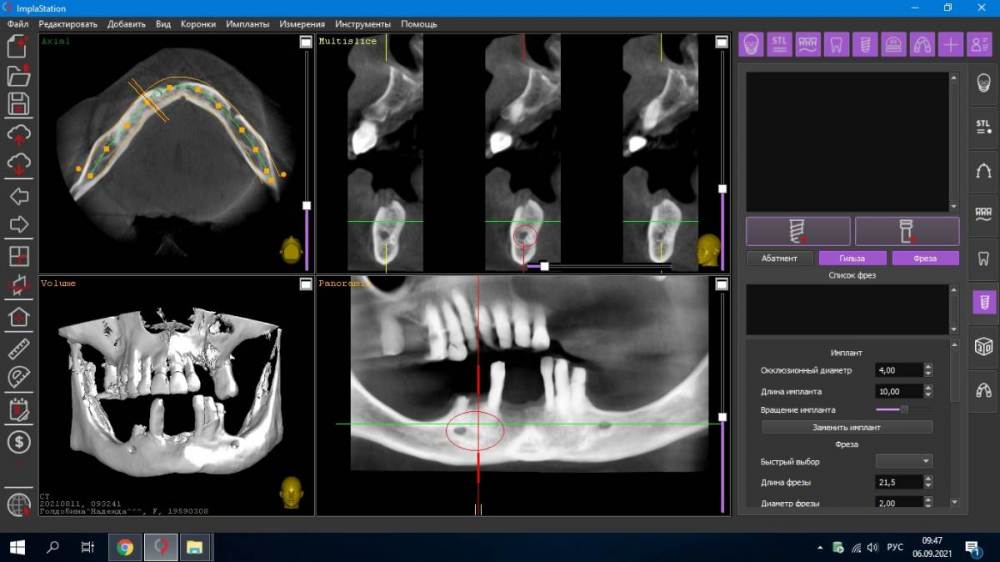

Fatal Опубликовано 6 сентября, 2021 Поделиться Опубликовано 6 сентября, 2021 (изменено) Доброго времени суток коллеги. Есть один клинический случай, где я планирую сделать все на 4, возможно с немедленной нагрузкой. Столкнулся с тем, что foramen mentale четко видно, но ''веточка'' от него выходит еще более медиально особенно в 4 квадранте (фото прилагаю) и тогда не получается поставить имплант в области 44 зуба под углом, что б шахта выходила более дистально для меньшего рычага. (планировалось закончить пятыми зубами или 6ки размоделировать как премоляры). Атрофия значительная в жевательном отделе, костные пластики не планируются. Импланты на фото расставлены примерно, для понимания картины. Вопрос: как ставить имплант в области 44 зуба, если '' веточка'' ментале выходит еще более медиально, также с зоной безопасности в 2 мм? (тогда я упрусь в имплант в области 41-42) -- 4 фото, обведено красным Изменено 6 сентября, 2021 пользователем Fatal Ссылка на комментарий

Александр07 Опубликовано 10 сентября, 2021 Поделиться Опубликовано 10 сентября, 2021 Ветку честно говоря не увидел, я бы больше наклонил имплантат, и длиннее, платформу импл максимально над менталисом расположить нужно постараться , это наиболее дистальное возможное положение Ссылка на комментарий